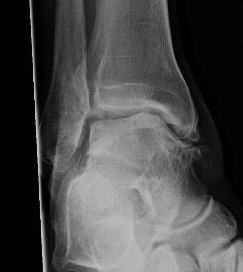

Chronic instability due to rupture of one or more parts of the lateral ligament

Progressive injury

1. Anterolateral capsule

2. ATFL

3. CFL

Can lead to ankle OA over time